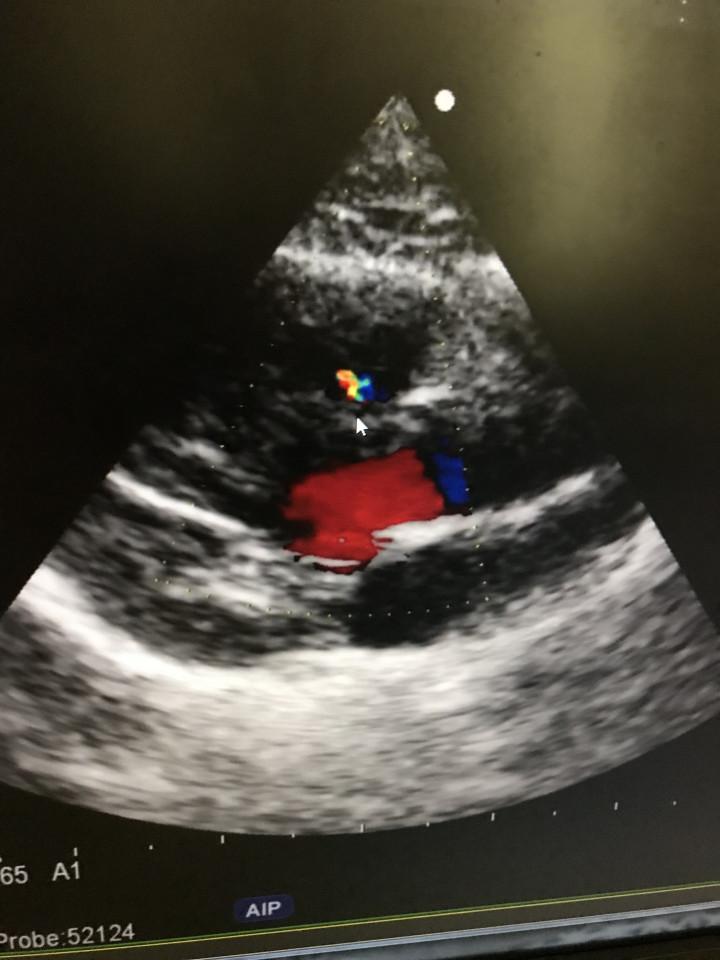

病気発覚当時のメルの心臓のエコー写真。

黄色と緑に見えるのが、本来流れ出てはいけない血液。

大量に流れ出てしまい、状態はかなり悪かったです。